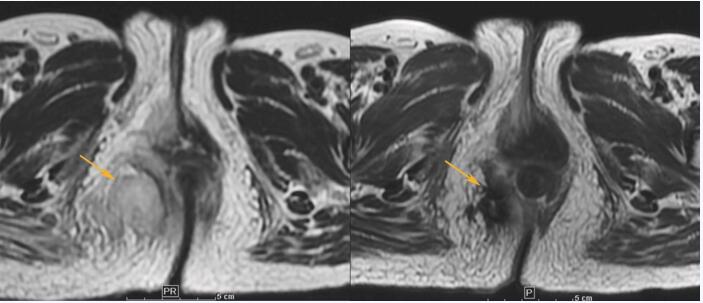

盆腔MRI:直肠距肛门约2cm处直肠环周增厚,呈结节状突向肠腔,病灶表面凹凸不平,累及长度约8.5cm,局部肠壁僵硬,肠腔变窄,浆膜面毛糙,病灶下极右侧向直肠腔外生长,局部形成软组织肿块,其内可见较大坏死腔。增强扫描可见明显不均匀强化,病变与子宫及阴道后壁脂肪间隙尚存在,骶前可见多发小淋巴结影(图2-A、图2-B)。

图2-A

图2-B